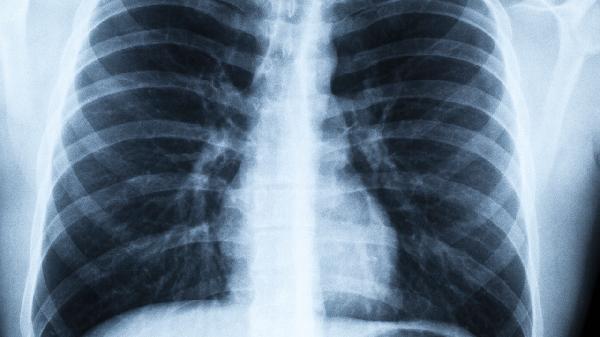

肺部毛玻璃样改变在影像学上表现为肺组织密度轻度增高,但仍能透过其看到支气管和血管结构。这种改变通常提示肺泡内气体被部分替代,或肺泡间隔增厚。常见于肺部感染如病毒性肺炎、细菌性肺炎,也可能由非感染性因素如过敏性肺炎、肺出血或吸入性损伤引起。部分患者可能因结缔组织病相关间质性肺病出现此类改变,少数情况下与早期肺腺癌相关。

持续性或进展性肺部毛玻璃样改变需警惕肿瘤性病变,尤其是当病灶呈现结节状或不规则形态时。特发性肺纤维化、肺泡蛋白沉积症等罕见疾病也可表现为弥漫性毛玻璃影。部分患者在胸部CT复查时可能发现毛玻璃影自行消退,这种情况多与一过性炎症或肺水肿有关。